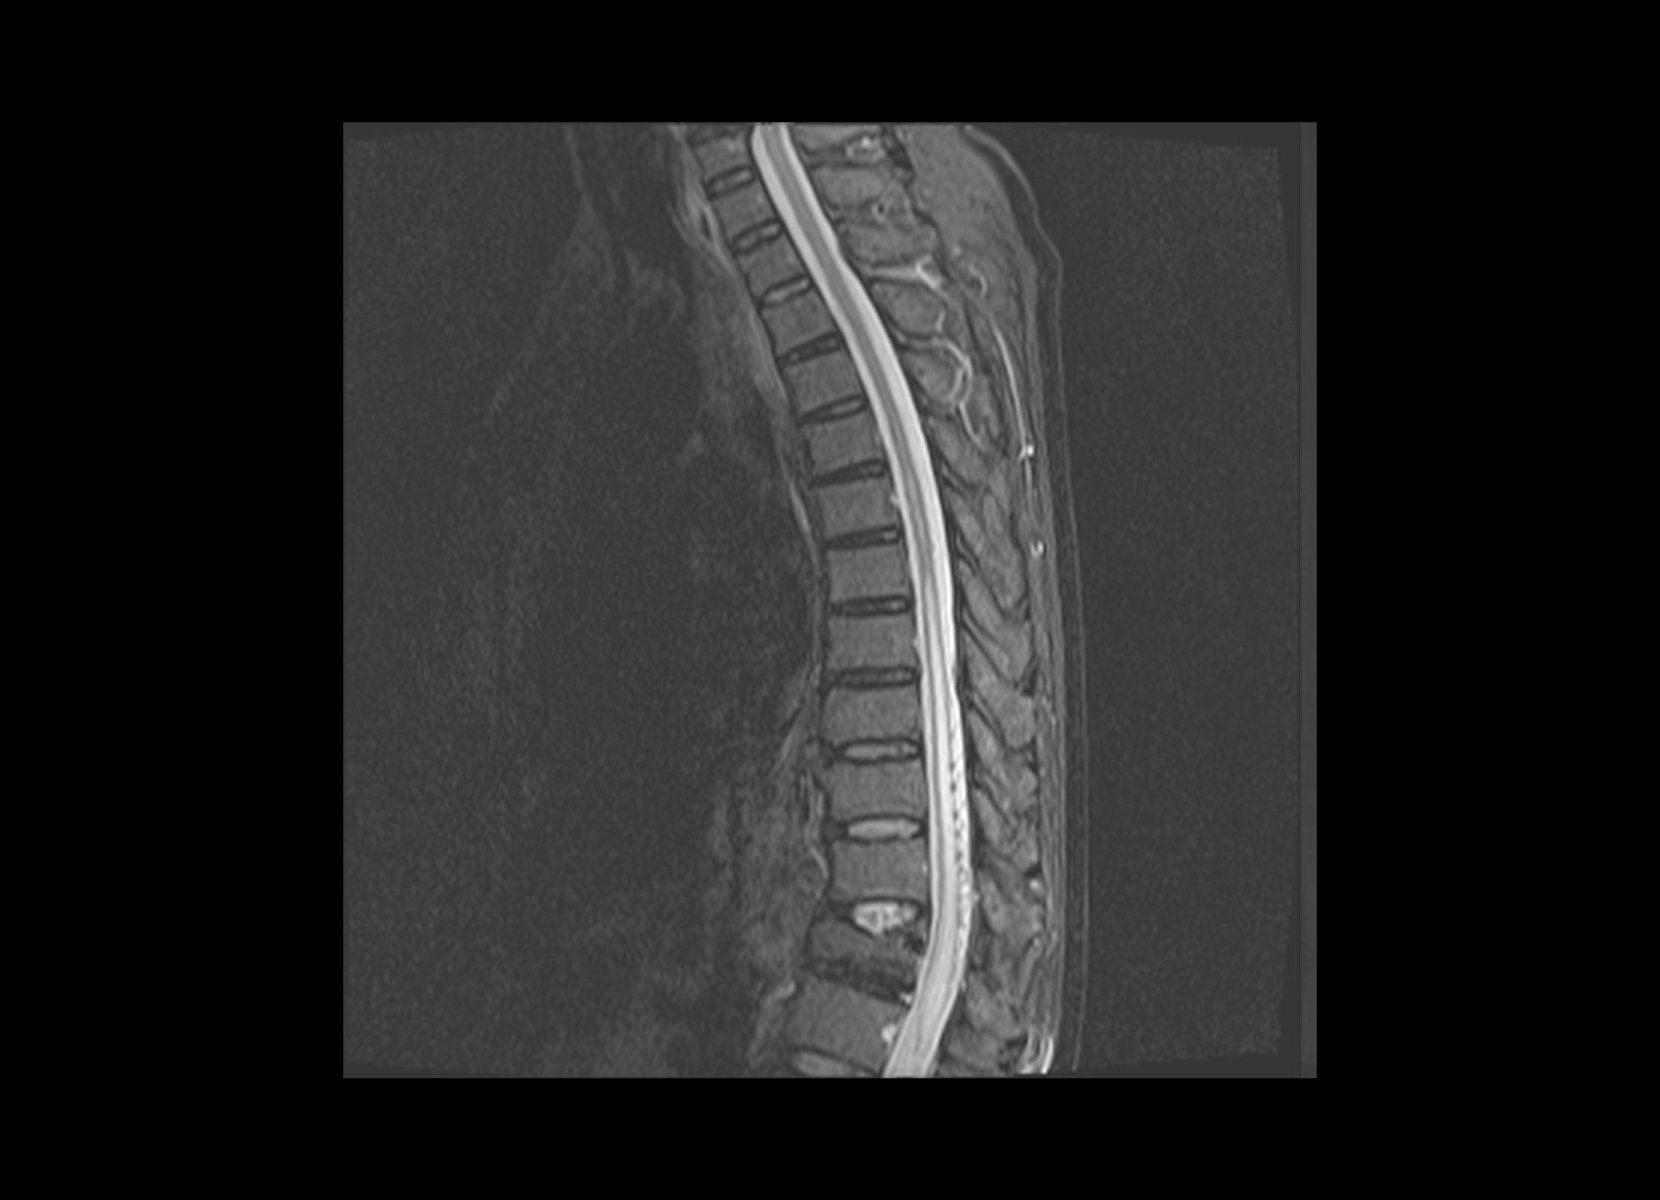

Conventional

STIR

SubtleSYNTH™

(Synthesized STIR)™

Cord lesion

GE 1.5T

C-spine